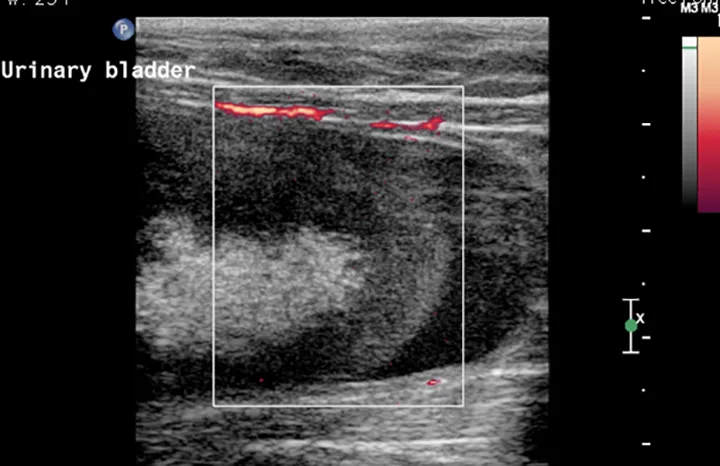

Treatment

Abdominal laparotomy with cystotomy was performed as the patient was no longer azotemic and his PCV had stabilized around 16% after receiving crossmatched packed red cells (Figure 4). The structure was removed and submitted for histopathology. The diagnosis was an organized hematoma; numerous erythrocytes and moderate numbers of neutrophils and macrophages surrounded by a fibrin layer were seen. Cultures of the bladder hematoma and urine were negative.

Figure 4. A 5 cm × 3 cm semifirm, rubbery structure is visible within the urinary bladder.